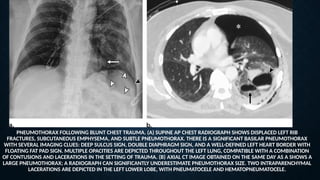

PNEUMOTHORAX FOLLOWING BLUNT CHEST TRAUMA. (A) SUPINE AP CHEST RADIOGRAPH SHOWS DISPLACED LEFT RIB

FRACTURES, SUBCUTANEOUS EMPHYSEMA, AND SUBTLE PNEUMOTHORAX. THERE IS A SIGNIFICANT BASILAR PNEUMOTHORAX

WITH SEVERAL IMAGING CLUES: DEEP SULCUS SIGN, DOUBLE DIAPHRAGM SIGN, AND A WELL-DEFINED LEFT HEART BORDER WITH

FLOATING FAT PAD SIGN. MULTIPLE OPACITIES ARE DEPICTED THROUGHOUT THE LEFT LUNG, COMPATIBLE WITH A COMBINATION

OF CONTUSIONS AND LACERATIONS IN THE SETTING OF TRAUMA. (B) AXIAL CT IMAGE OBTAINED ON THE SAME DAY AS A SHOWS A

LARGE PNEUMOTHORAX; A RADIOGRAPH CAN SIGNIFICANTLY UNDERESTIMATE PNEUMOTHORAX SIZE. TWO INTRAPARENCHYMAL

LACERATIONS ARE DEPICTED IN THE LEFT LOWER LOBE, WITH PNEUMATOCELE AND HEMATOPNEUMATOCELE.